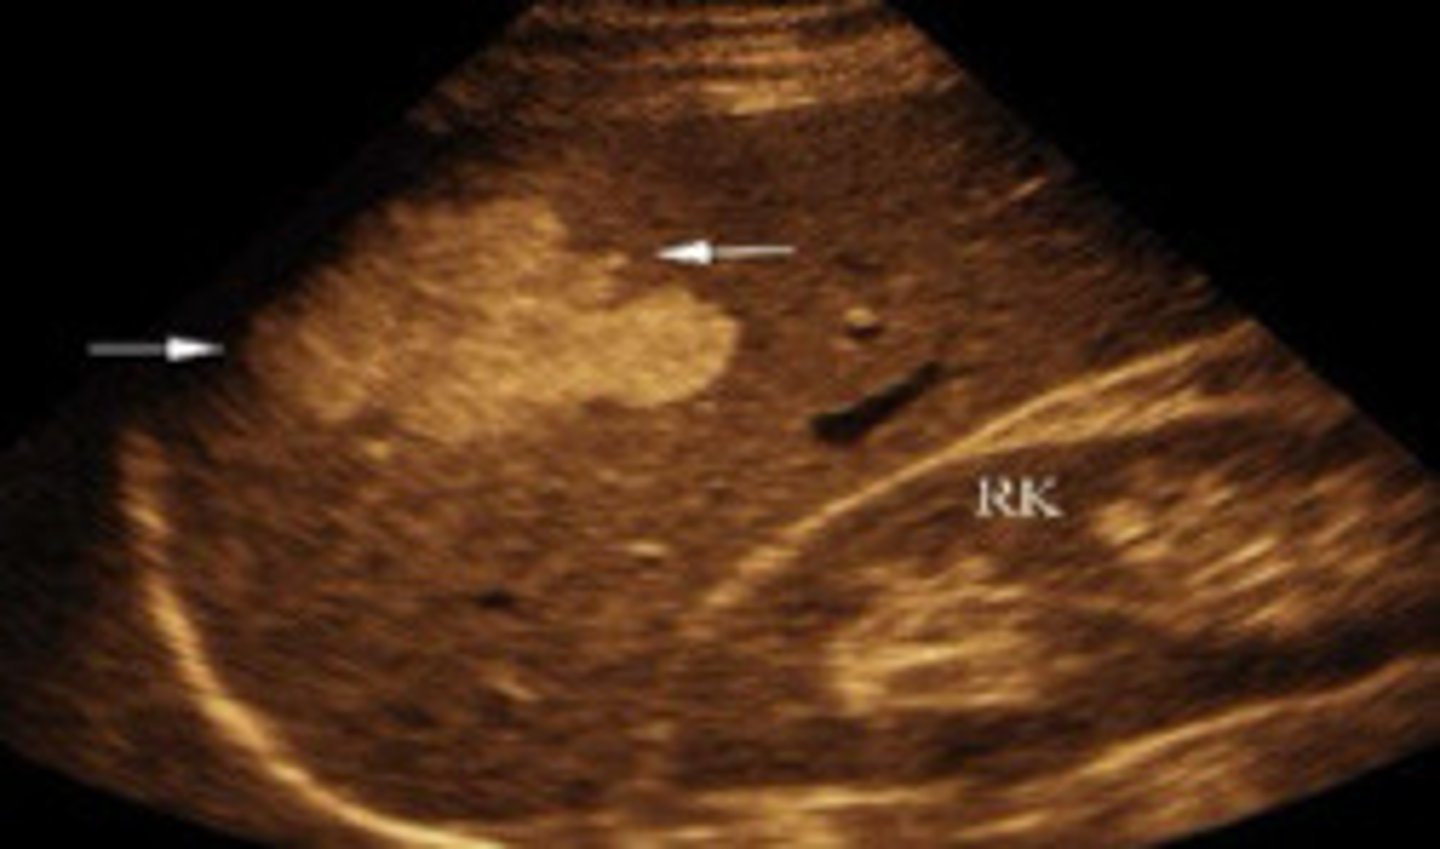

Hemangioma in the spleen

What does this image show

Hemangioma in the spleen (see with contrast study)

Larger and more complex usually than as seen in liver

Compare the sonographic appearance of a hemangioma in the spleen as compared to one in the liver